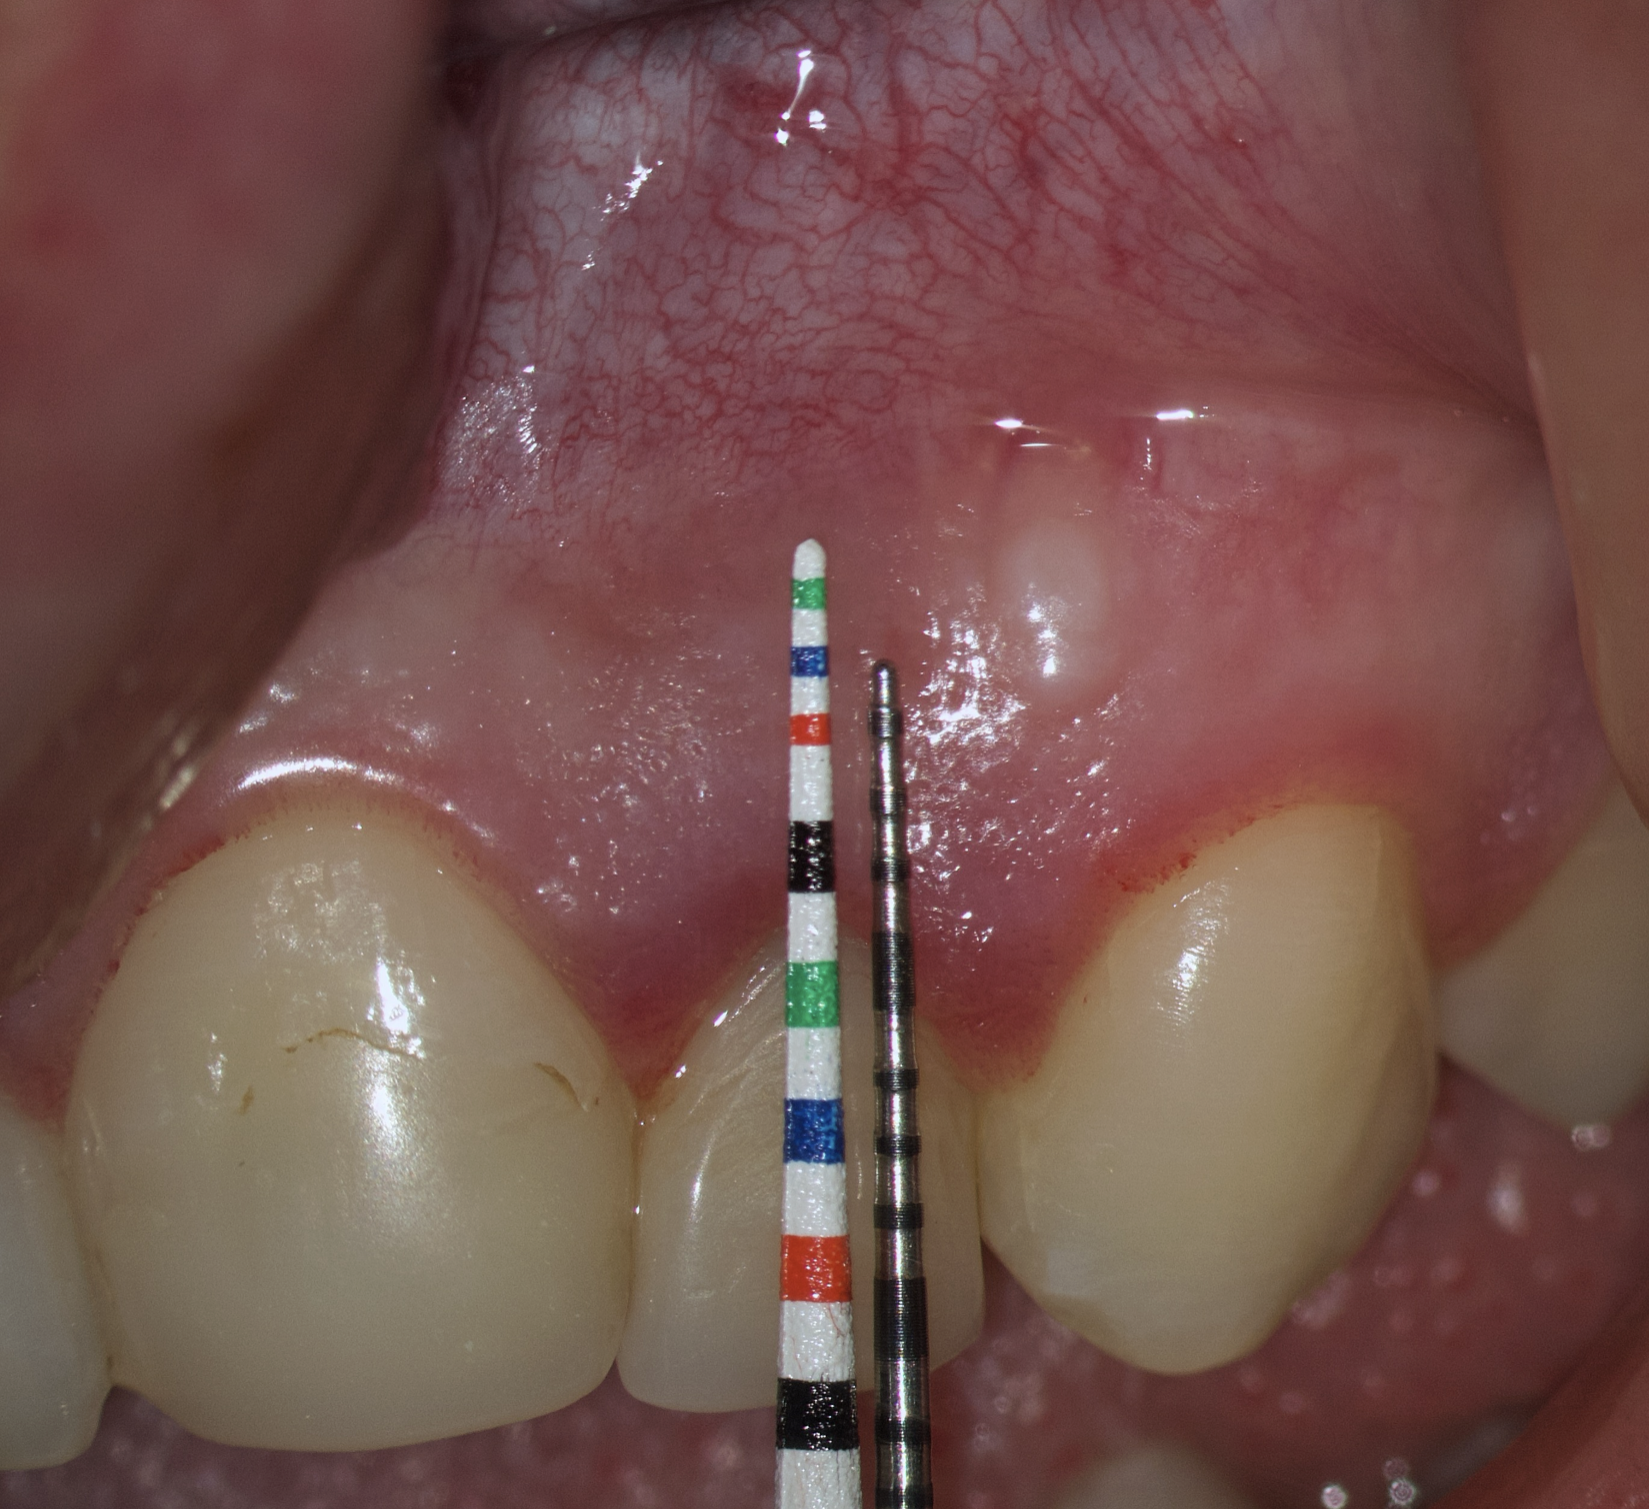

Therefore, the selection of this type of incision requires thorough treatment planning [12]. To avoid the incision falling into an existing bone defect or a defect created by an osteotomy, it is rational to plan a submarginal incision. We can determine whether we can make it, according to the clinical situation of a patient by following approach. To do this, first we need to determine on the CBCT where the bone defect is located or where the osteotomy will take place. Then, using a virtual ruler, measure the distance from the incisal edge of the tooth on which the intervention will be performed to the beginning of the bone defect or osteotomy (Fig 7).

We transfer this distance is transferred to a metal probe and fixed with an endodontic stopper. Next, we take a plastic probe and substitute it near the zenith of a tooth on which the intervention will be performed at a mark of 6 mm (3 mm must be retreated to perform a submarginal incision and another 3 mm is needed for the formed flap to overlap healthy bone tissue) (Fig 8).

We compare the lengths of the plastic and metal probes. The first option is when the metal probe is above the plastic one, then we can assure that the incision and the Ochsenbein-Luebke flap will accurately cover the bone defect and the submarginal incision is safe (Fig 9).

The second option is when the lengths of both probes are the same. This option is when a tooth has previously undergone root apex resection or a root is anatomically short or there is extensive periapical lesion. Under these conditions, we understand that there is still a safe distance of 3 mm so that the formed Ochsenbein-Luebke flap will also cover the bone defect and therefore, we can perform a submarginal incision and flap (Figs 10 and 11).